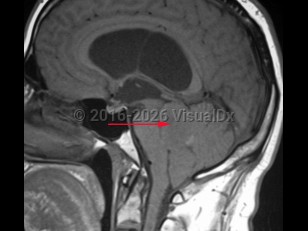

EpendymomaEpendymoma

NeurocysticercosisNeurocysticercosis

Subarachnoid hemorrhageSubarachnoid hemorrhage